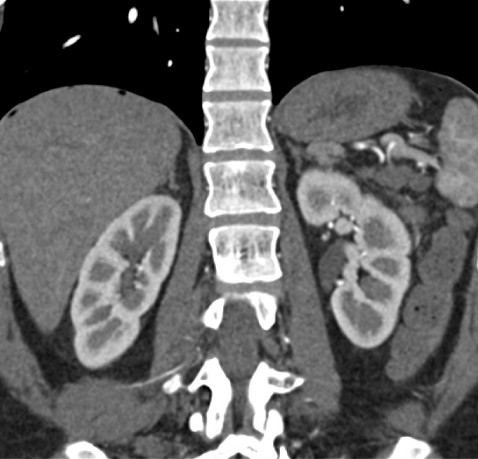

КТ органов забрюшинного пространства – что выявляет обследование

На снимках хорошо визуализируются почки, лимфоузлы, надпочечники, сосуды. Диагностика показывает дефекты строения и развития органов, абсцессы, конкременты в протоках, почках, кисты, опухолевые образования, а также патологии лимфатической системы, которые связаны с заболеваниями крови.